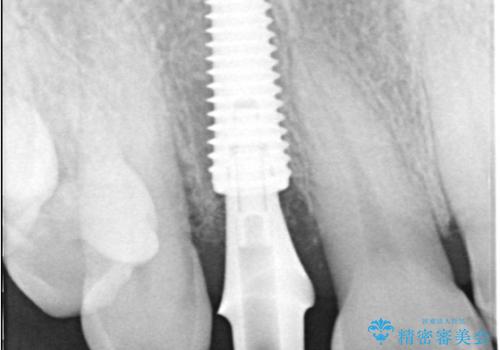

インプラント治療は、低侵襲で短期間に行える「抜歯即時インプラント治療」を選択しました。

この方法は、抜歯したその日にインプラントを埋入し、手術が1回で済むのが大きな特徴です。

治療期間も短く、抜歯からわずか3か月でオールセラミッククラウンを装着することができます。

また、オペ当日には仮歯まで装着するため、見た目を気にせず普段通りの生活を送ることができます。